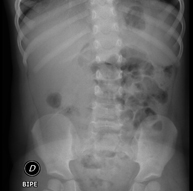

- Abdomen i pelvis

- RX Abdomen

Tècnica que usa els raigs X a través de la qual s'obtenen imatges de l'abdomen (estómac, intestí prim, intestí gros, fetge, ronyons, bufeta, pelvis òssia, etc.) per al seu estudi. - RX Columna lumbar

Una radiografia de tòrax és una tècnica mitjançant la qual, amb l'ús d'una petita dosi de radiació, s'obté una imatge bidimensional de la caixa toràcica i el seu contingut (pulmons, cor, mediastí, etc. ). És una de les proves mèdiques realitzades més comuna. - RX Abdomen

Una radiografia d'abdomen és una tècnica mitjançant la qual, amb l'ús d'una petita dosi de radiació, s'obté una imatge bidimensional de l'abdomen amb les seves estructures anatòmiques (estómac, intestí prim, intestí gros, fetge, pàncrees, ronyons, bufeta, pelvis òssia, etc.) - Telerradiologia columna